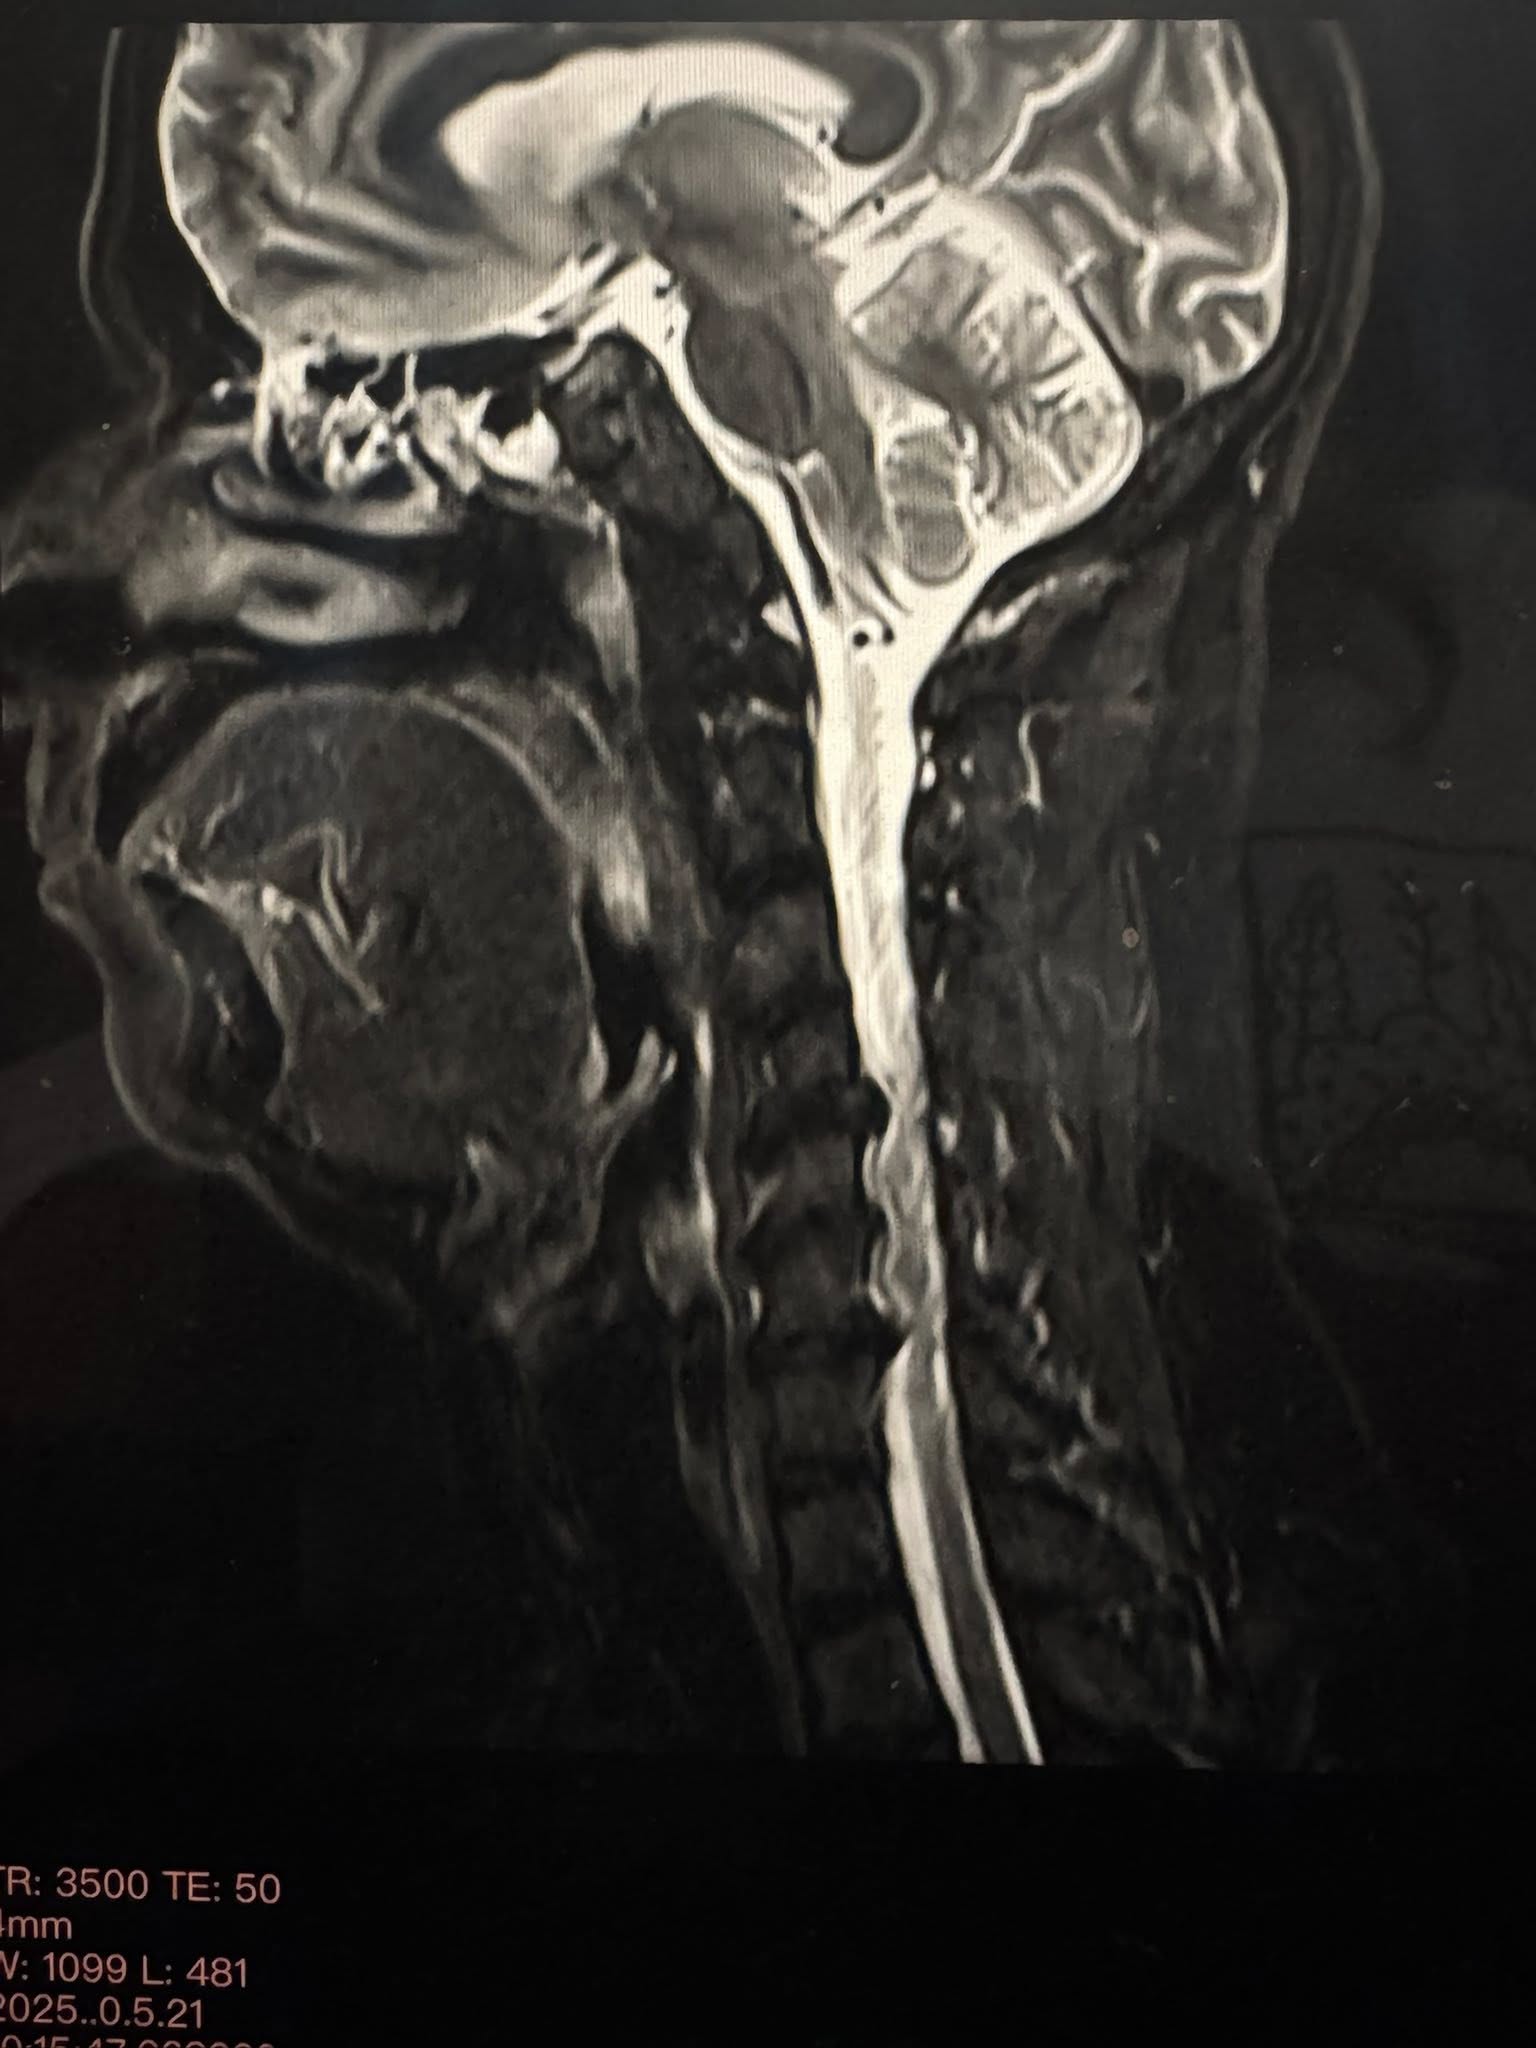

न्यूरोसर्जरीजस्तो जटिल शल्यक्रिया सहज हुँदैन । गर्धनको ‘सर्भाइकल स्पाइन’ मा तीन तहमा ‘हर्निएटेड डिस्क’ देखिनु गम्भीर विषय हो, जसले अंग सुन्निनु, पीडा र शरीरको गतिशीलतामा प्रभाव पार्न सक्छ । त्यसैले सर्जरीलाई चुनौतीपूर्ण मानिएको थियो । तर तीन पूर्वविद्यार्थीहरूले गरेको सहकार्य र समर्पणले शल्यक्रिया सफल भयो ।